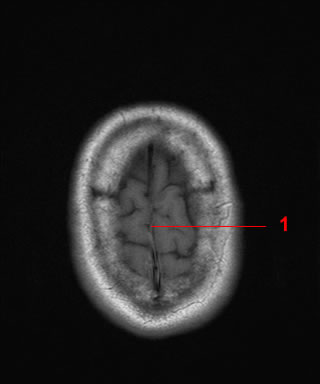

11. What structure is indicated by the arrow in the image?

The correct answer is 'Meningioma' because the arrow is pointing to a tumor within the brain, not a specific structure such as the frontal horn of lateral ventricle, anterior limb internal capsule, or thalamus.